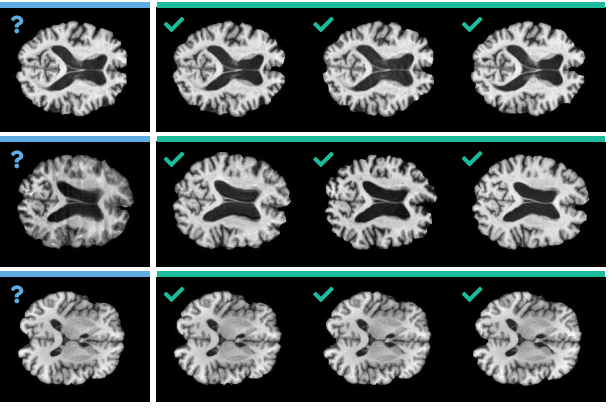

DeepBrainPrint è un framework di deep learning contrastivo per la ri-identificazione di soggetti tramite MRI cerebrali, accettato alla conferenza Medical Imaging with Deep Learning (MIDL) 2023. Nel panorama del brain fingerprinting, DeepBrainPrint rappresenta il primo approccio semi-auto-supervisionato, capace di estrarre una “impronta numerica” dalla morfologia cerebrale che consente il recupero efficace di tutte le scansioni relative allo stesso soggetto da grandi dataset di imaging medico.

- Pipeline contrastiva semi-auto-supervisionata, che combina apprendimento self-supervisionato e supervisione debole per creare rappresentazioni numeriche (fingerprint) robuste della morfologia cerebrale.

- DeepBrainPrint supera tecniche di deep metric learning all’avanguardia (InfoNCE, SoftTriple, SimCLR, BarlowTwins) sia in accuratezza, sia in efficienza computazionale e capacità di generalizzazione su soggetti diversi.